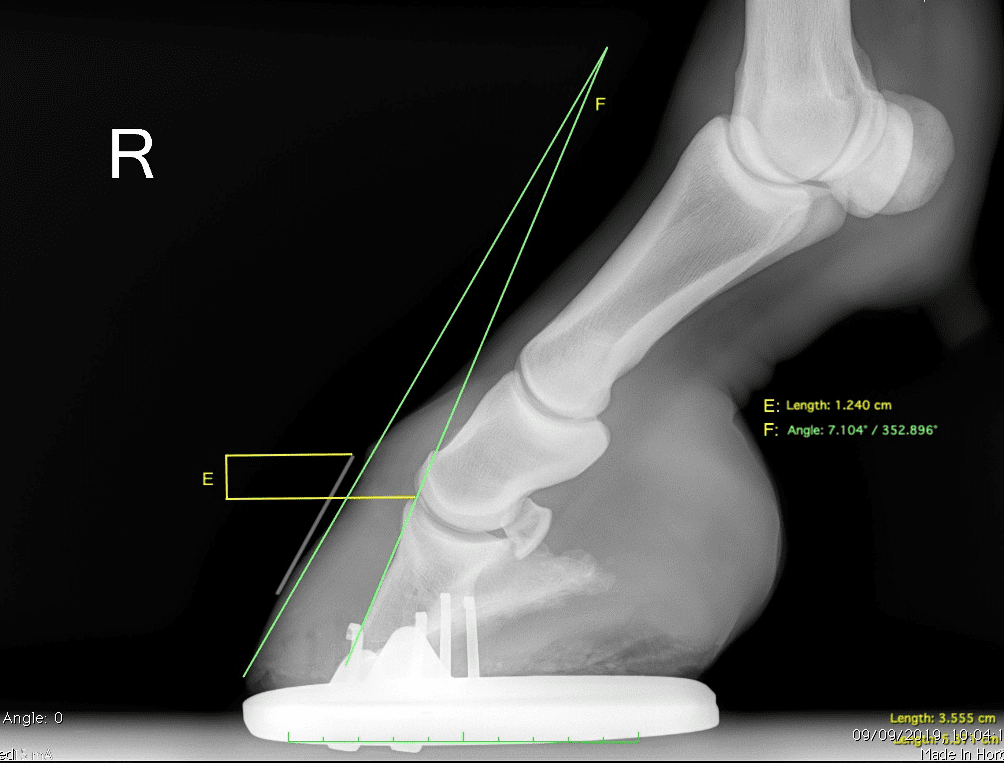

Innovative Equine Podiatry Acute Laminitis Case Study